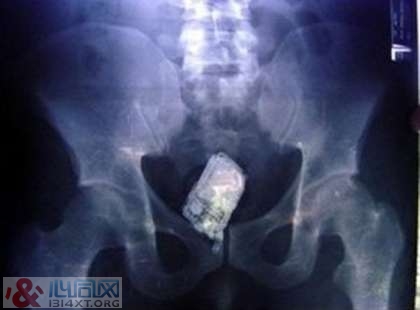

6. 一支手机